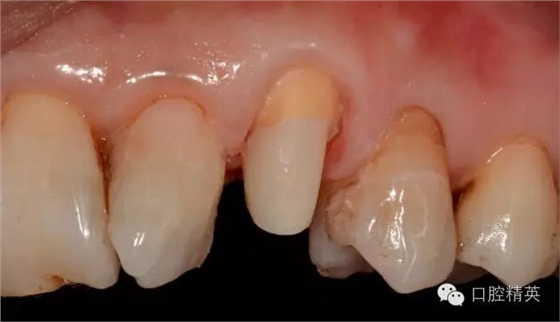

圖123口內(nèi)修復(fù)前情況:殘根位于齦上3MM,牙周無(wú)紅腫.

口內(nèi)檢查: 23殘根,位于齦上3MM,根管口探無(wú)反應(yīng),叩(+-),無(wú)松動(dòng),牙周無(wú)紅腫.X片示:23根管無(wú)阻射,根尖骨密度降低.

11.12.13頸部楔形缺損,探敏感,牙髓活力正常.